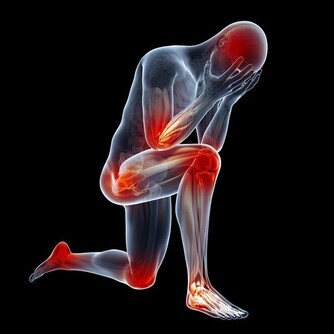

傳統醫學認為桑椹味酸,性微寒,具有提高人體免疫力、補血滋陰、生津止渴、潤腸燥等功效,主治陰血不足而致的頭暈目眩、耳鳴心悸、煩躁失眠、腰膝酸軟、鬚髮早白、消渴口乾、大便乾結、滋陰補血、明目安神、利關節、去風濕、解酒等功效,在《中國大藥典》、《本草拾遺》、《滇南本草》、《唐本草》等醫學典籍中均記載有桑果的防病保健功能。

桑椹具有補肝益腎、生津潤腸、烏髮明目、止渴解毒、養顏等功效,適用於陰血不足、肝腎陰虧、腰膝酸軟、目暗耳鳴、頭暈目眩、盜汗及津傷口渴、消渴、腸燥便秘等症。